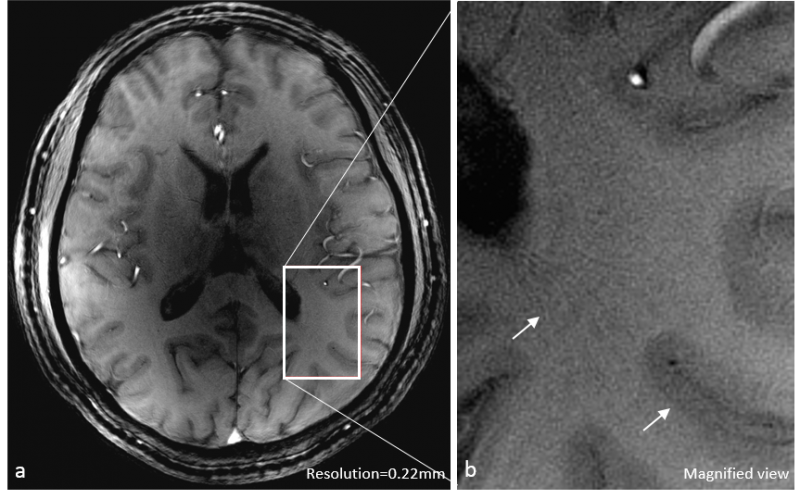

Qian's Lab for MRI at the General Labs Cloud, LLC announces a new technology that produces high resolution MRI images for the brain and knee at an ultrashort echo time (<1 ms). The high resolution UTE images can be used in clinical research to detect subclincal injuries/defects in cartilages of the knee or in parenchyma of the brain, without impact from edema fluids. The technology includes a pulse sequence and a computer program for image reconstruction. Data acquisition is based on an acquisition-weighted stack of spirals (AWSOS) pulse sequence, which is applicable to MRI systems at 3 Tesla or higher. This technology was invented by Dr. Qian and colleagues, patented in the United States (Patent No.: US7750632), and owned by the University of Pittsburgh, Pittsburgh, PA. Therefore, only lease is availabe to customers.

Figure (left): High-resolution UTE image of a healthy knee at 3T (TE = 0.6 ms, in-plane resolution = 0.14 mm, and slice thickness = 2.0 mm). Figure (right): High-resolution image of a healthy brain at 7T (TE = 1.1 ms, in-plane resolution = 0.22 mm, and slice thickness = 2.0 mm).